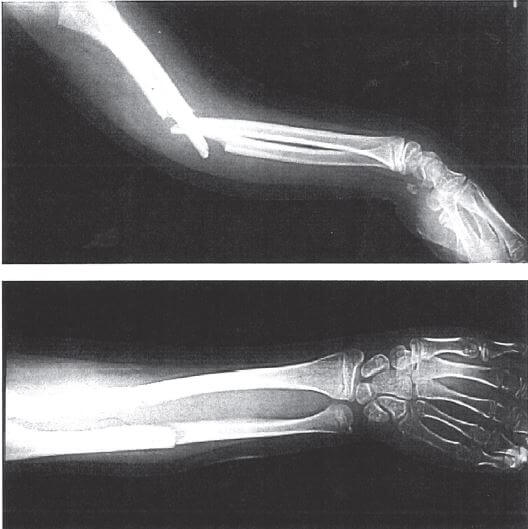

問題80.15歳の男子。受傷直後の単純エックス線写真を下に示す。

正しいのはどれか。

1.典型的な直達外力による骨折である。

2.腕頭関節脱臼を合併するものが多い。

3.外固定は前腕近位部から手関節までの範囲とする。

4.前腕両骨間の癒合を予防する。

解答4

1.× 典型的な「直達外力」ではなく介達外力による骨折である。なぜなら、本症例の単純エックス線写真では、異なる高さで斜走して骨折しているため。また、前腕両骨骨折は多くの場合、転倒して手をついた際のねじれ力・曲げ力(介達外力)によって起こる。直達外力(直接打撃)による場合は、通常、骨折部が同一高位で横骨折になることが多い。

2.× 腕頭関節脱臼を合併するものは、「モンテギア骨折」の特徴である。本症例は、橈骨・尺骨ともに骨幹部骨折で、脱臼を伴っていない。

・モンテギア骨折とは、尺骨骨幹部骨折に橈骨頭前方脱臼が起きたものである。手をついて転倒・転落した際、前腕回内力が作用することで起こりやすい。

3.× 外固定は、「前腕近位部」ではなく肘関節から手関節までの範囲とする。なぜなら、前腕両骨骨折では、前腕の回内外運動も制限する必要があるため。前腕の回内外運動により、橈骨・尺骨と剪断力が加わり治癒に支障をきたす。

4.〇 正しい。前腕両骨間の癒合を予防する。なぜなら、橈骨と尺骨の間には骨間膜があり、整復不良や手術操作によって両骨が接触・癒合すると、前腕の回内外運動(回旋運動)が失われるため。